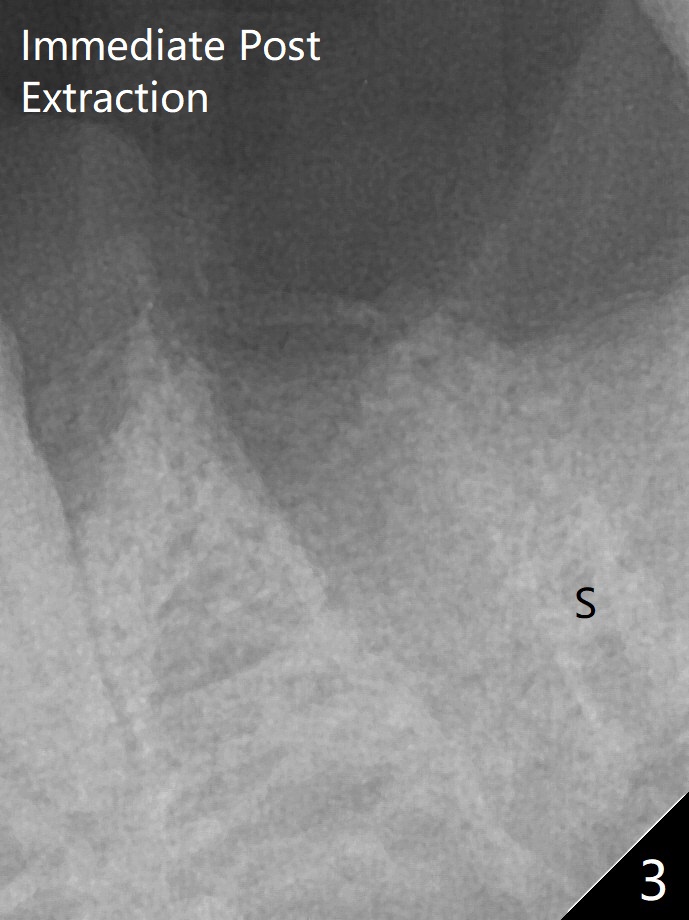

术后三个月牙槽嵴宽(图六);高度稍微减低(图七)。